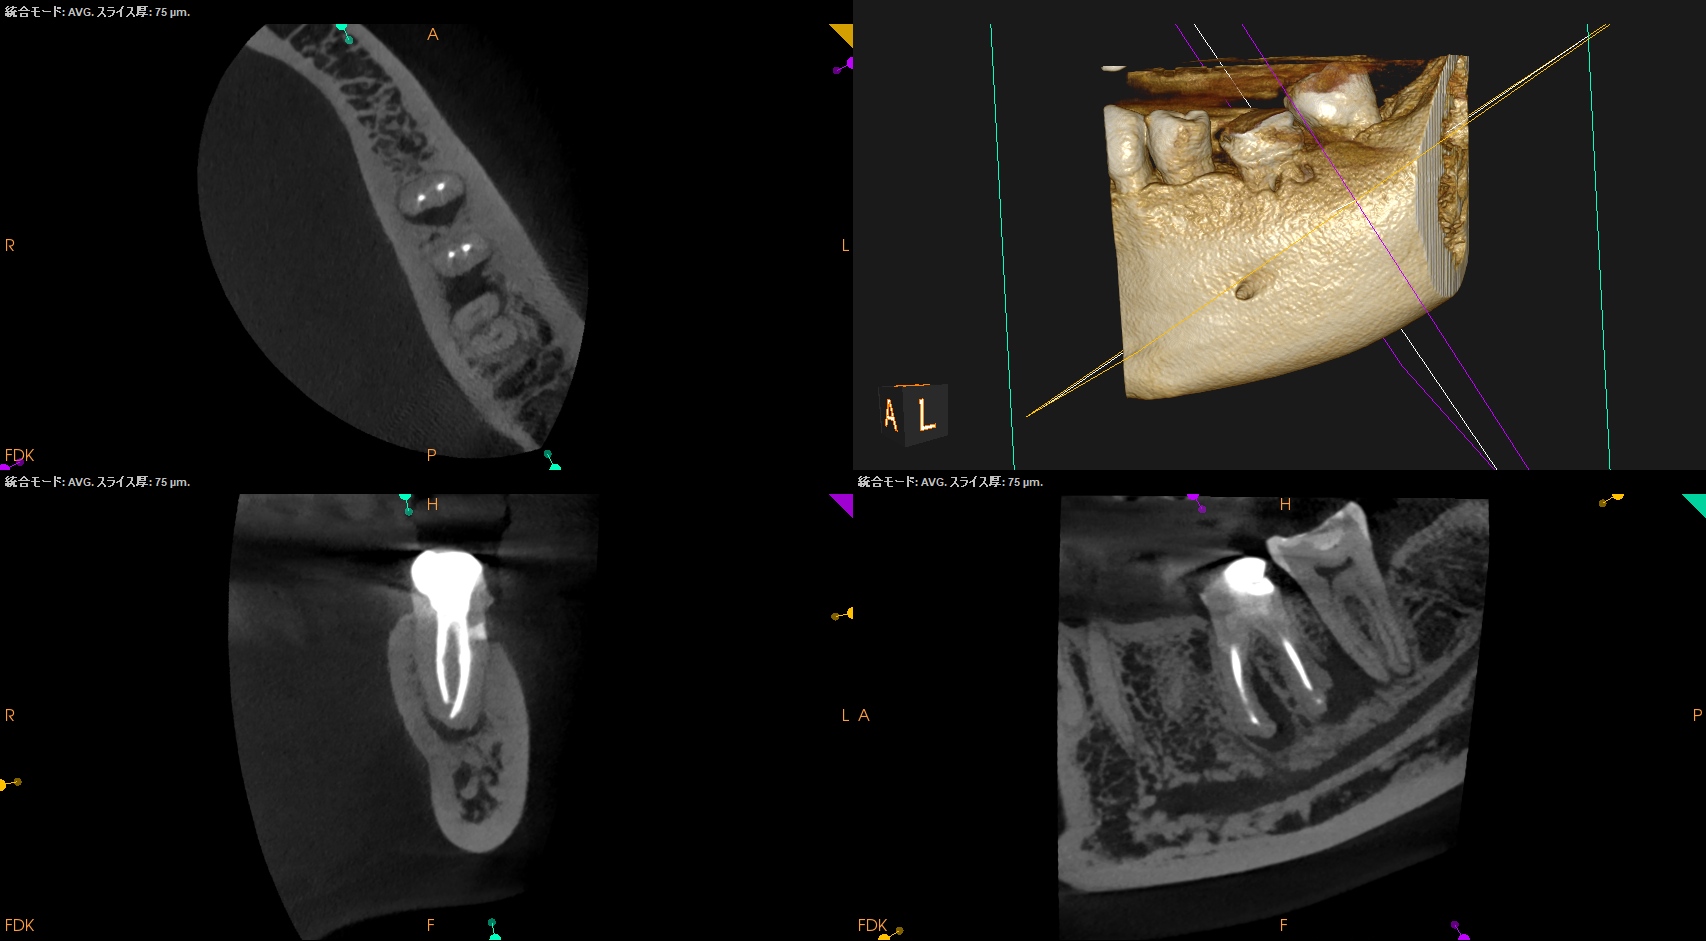

前回、前々回の記事で歯内療法におけるCBCTの有用性について論じたが、

今日はその応用編をご紹介する。

穿孔しているのだろうか?とまず思ったが、CBCTをみてそれは穿孔でなく外部吸収の可能性が高いと判断できた。

もはや全ての歯内療法の処置前には必ずCBCTが必要

これらの画像的事実と臨床検査から

1. まず外部吸収を封鎖する

2. その後(その日に)、再根管治療を行う

という治療計画を提示し、患者さんが同意していただいたのでまずは外科だ。

術後にPA, CBCTを撮影した。